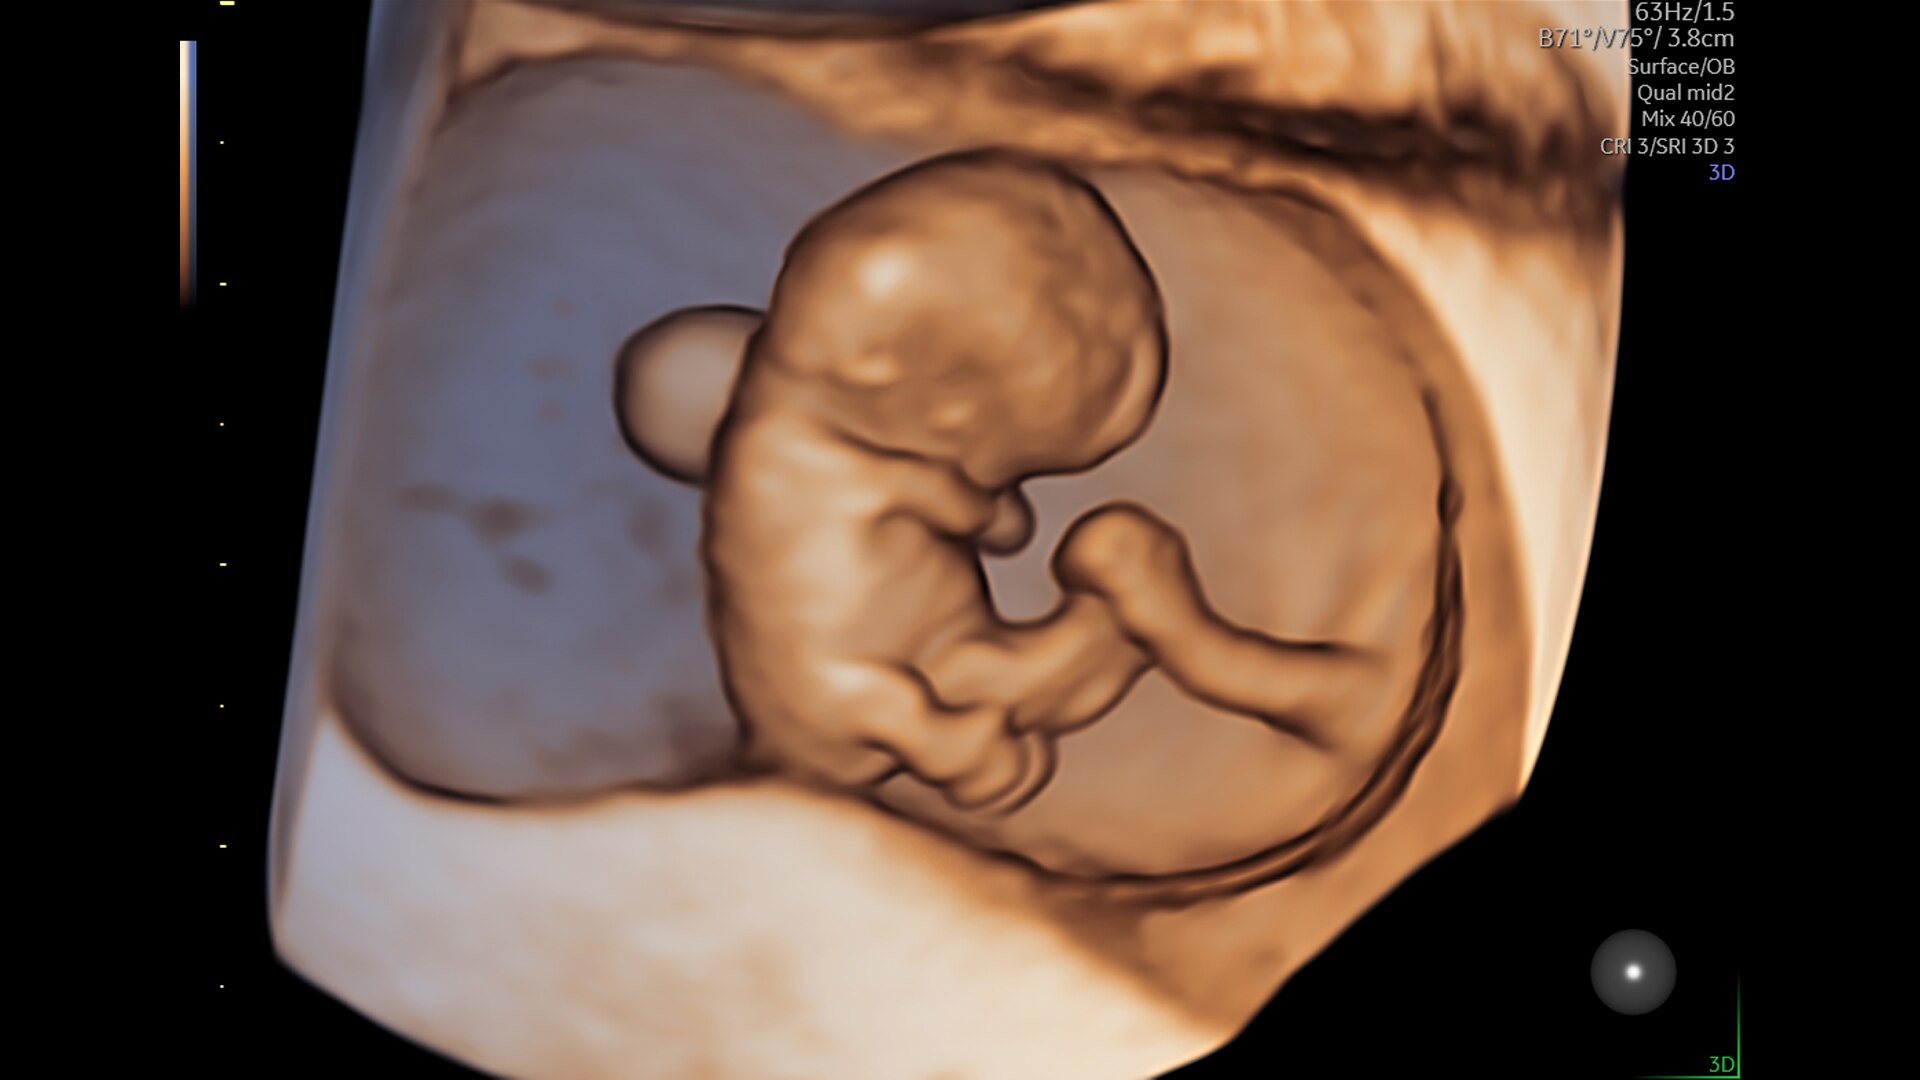

Les cas complexes apportent leur lot d'incertitude. C'est pourquoi le Voluson Expert 22 est spécialement conçu pour réaliser une évaluation approfondie de l'anatomie complexe, avec des technologies innovantes pour l’examen du premier trimestre, l’évaluation de la fonction cardiaque fœtale, l’examen gynécologique et d’autres technologies révolutionnaires ciblées sur la détection et l'intervention précoces.

En bref